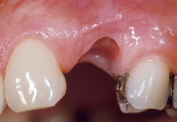

Für den Knochenaufbau wurde Geistlich Bio-Oss Collagen in den Defekt appliziert und nach der Augmentation die Eingriffsstelle mit einem Kollagenvlies abgedeckt. Weitere 6 Monate nach dem Eingriff wurde die endgültige Kronenrestauration eingesetzt. Bei der weiteren Nachuntersuchung nach nunmehr 25 Jahren zeigte die Röntgenaufnahme ein stabiles Implantatlager und das klinische Bild bei der Nachkontrolle einen ästhetischen Zahnstatus.